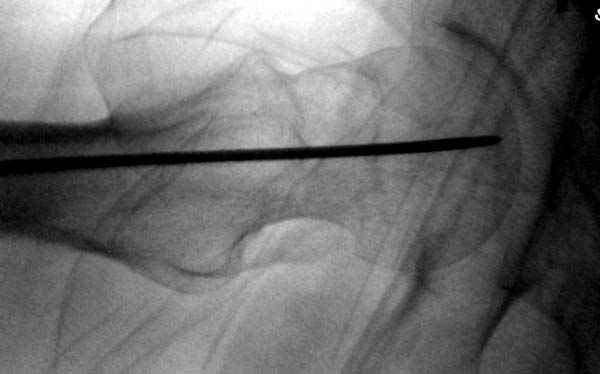

На второй день после выписки упал дома. Снимки приложены. Коллеги рекомендуют удаление шурупа и вытяжение. Что делать?

Привет из солнечного Будапешта с Eurotrauma-2008. Да, замечательный пример. Получается, профилактику расхождения отломков шейки надо было проводить каким-то реконструкционным или проксимальным гвоздем, причем сразу длинной версией. Сейчас, наверно, так и надо бы сделать.

Убрать винты, каким-то джойстиком в вертельной области сделать репозицию шейки, фиксировать ее спицами, а дальше вправлять и фиксировать как вертельный перелом.

Решайте проблемы по мере поступления. На первом этапе решение одно, и на мой взгляд верное. Ситуация изменилась кардинально - другое решение. Я бы избрал ресинтез, убрав винты заменил на Гамму. Что с ним будет послезавтра? - Будем решать послезавтра. Такая наша доля.

"Решайте проблемы по мере поступления. На первом этапе решение одно, и на мой взгляд верное. Ситуация изменилась кардинально - другое решение. Я бы избрал ресинтез, убрав винты заменил на Гамму. Что с ним будет послезавтра? - Будем решать послезавтра. Такая наша доля."

Правильно, ситуация изменилась, как говорят у нас теперь "different animal", надо решать проблему подвертельного перелома. При наличии различных вариантов фиксаторов, включая Страйкер Гамма 3, мы выбрали DePuy Antegrade Trachanteric Nail из-за многовариантности проксимальной фиксации и двойного изгиба. Вводится через вертел под 8 градусным углом, и есть достаточный передний диафизарный изгиб, предупреждающий пенетрацию дистального переднего кортекса.

Но ведь и головка бедра сползла в варус - отчего ограничились только фиксацией подвертельного перелома, а не убрали винты и не сделали репозицию шейки?